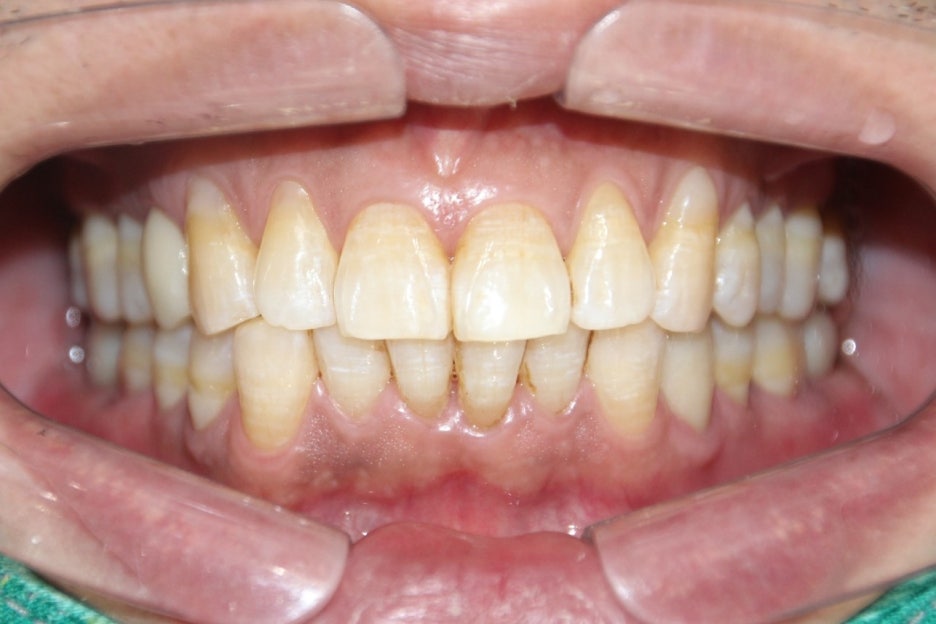

이제는 깨끗해진 모습이 보여집니다.

양치할 때, 피가 나고 냄새가 나면

구강 건강에 이상이 생겼을 가능성이 높습니다.

일시적인 현상으로 출혈이 발생할 수 있지만,

약한 칫솔질에도 출혈이 발생하는 건

잇몸이 약해졌다는 것을 의미합니다.

잇몸은 치아를 단단하게 붙잡아주는

역할을 합니다.

이러한 잇몸이 약해지게 되면 치아도 결국

흔들리게 됩니다.